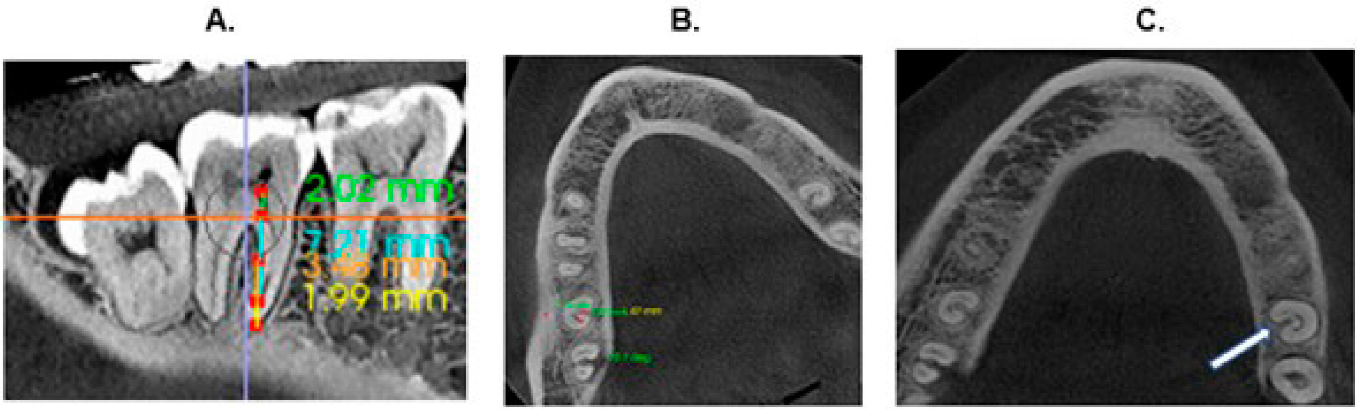

La configuración del canal en forma de C se categorizó en vista longitudinal y cortes axiales radiculares en tres niveles: coronal, medio y apical (Figura 1). Coronal (C): a 2 mm del piso de cámara pulpar; Medio (M): La mitad de la longitud radicular desde C hasta A; Apical (A): a 2 mm del ápice14,15.

Figura 1 A. Vista sagital de la CBCT que ejemplifica los tres niveles en los que se realizó la evaluación coronal, medio y apical. B. Corte transversal en tercio medio para análisis de clasificación tipos II y III según Fan et al en 2004. C. Corte transversal en tercio medio para análisis de presencia de surco (flecha).